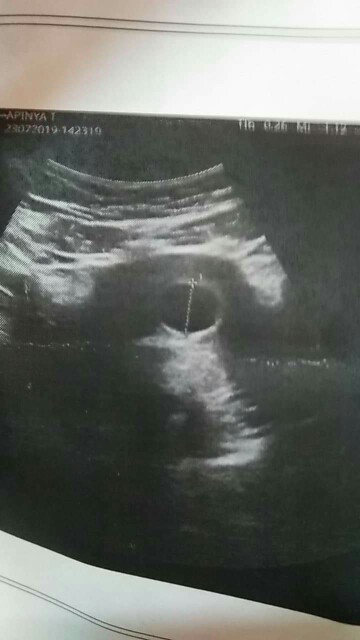

อัลตร้าซาวด์ไม่เจอเด็ก

ไปฝากครรภ์ตอน6w+6 อัลตร้าซาวด์เจอแต่ถุงค่ะ กังวลมากๆ กลัวท้องลมหรือแท้ง ?? #อัพเดตจ้า ตอนนี้น้องคลอดแล้วนะค่ะ. ? น้องข้าวแป้งอภิสรา 12กุมภาพันธ์63จ้า

รอซัก 8 วีค ลองไปซาวด์ดูอีกทีนะคะ นี่ของเราตอน 6 วีคค่ะ